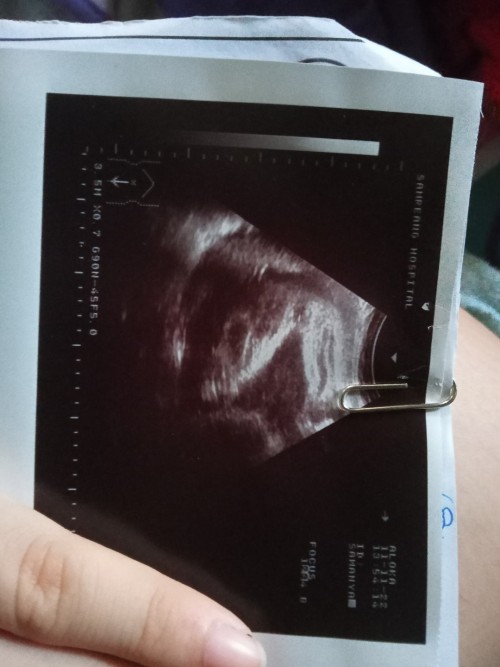

หญิงไหมคะแบบนี้...32wท้องเเรก อยากได้หญิง😁😁😘😘 ขอดูผลซาวด์ของแม่ๆหน่อยจ้า #ขอบคุณล่วงหน้านะคะ

บ้านนี้ผู้หญิงเหมือนกันค่ะ

ลูกสาวค่ะ 💕👧